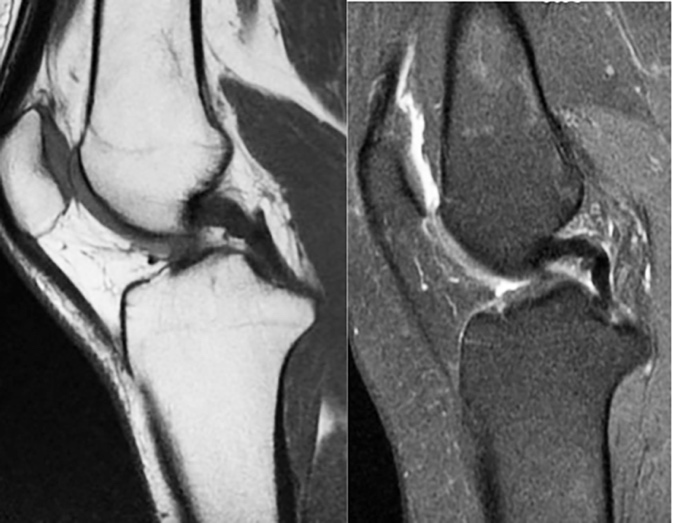

La resonancia magnética permite visualizar los LMFs sin necesidad de disección anatómica. En RM, con cortes en densidad T2, el LCP normal aparece como una estructura uniforme bien definida con una señal de intensidad baja. Cuando está relajado en extensión muestra una curva de convexidad posterior. Una estructura pequeña redonda u oval de baja intensidad se puede apreciar, a menudo, por delante o por detrás del LCP; son los LMF que discurren oblicuamente desde el cuerno posterior del menisco lateral al cóndilo medial [19] (Figura 5) (Figura 6).

El LMFp además de su presencia o ausencia, tiene formas y tamaños muy diferentes, asociado con la interposición de una imagen de una franja de grasa entre el LMFp y el cuerno posterior del menisco lateral [20][21]. El fascículo oblicuo del LCP se confunde, también en disección, con el LMFp [12][22-24]; es más, Hassine et al.[20] describen la fusión de estas dos estructuras.

El LMFp es visible y está separado del LCP, es pequeño de forma ovoide con señal poco intensa, inmediatamente por detrás del LCP y el anterior aparece como un bulto discreto de baja señal a lo largo de la superficie cóncava del LCP o como una pequeña formación ovoide de baja señal justo por delante del LCP. Cuando son visibles en RM, el LMF anterior (LMFa) y el posterior tienen una inclinación diferente debido al distinto punto de inserción en el cóndilo femoral lateral; la oblicuidad del LMF posterior es más acentuada que el anterior [27]Para Kaplan et al., [28] el LMFa se origina del LMFp, como si fuera su rama anterior; Gupte et al., [13] los consideran estructuras independientes que coexisten en el 50% de las rodillas, con orígenes e inserciones individualizados. Lahlaidi y Vaclavek [5] proponen una explicación embriológica para comprender las variaciones anatómicas observadas, sugiriendo que el sitio del LCP durante el desarrollo embriológico determina la presencia y posición de los LMF.

Corbi y Forriol [32][33] en un estudio anatómico y en RM la presencia del LMFp fue más frecuente. En las piezas anatómicas se encontró el LMFp en el 72,41% y en RM, en el 55,68%. Por su parte, el LMFa se vio en el 20,68% de las piezas anatómicas y en el 30% de las RM. Ambos conjuntamente se demostraron en las piezas anatómicas en el 13,8% y en la RM en el 22,5%.